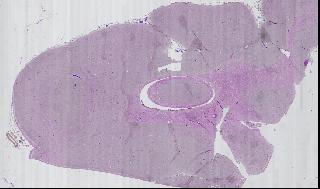

Figure 5

Using this tool, we can zoom out to view the entire slide, zoom in on a specific region of a single sample, then view a specific field of vision. Figure 5 is a mosaic of one portion of one slide.